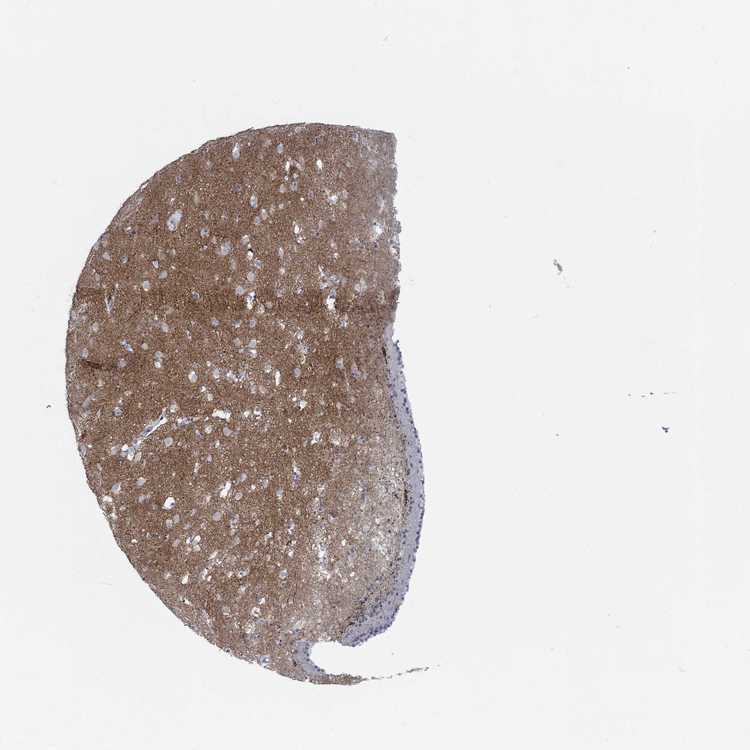

TISSUE PRIMARY DATA CAUDATE Show tissue menu

CAUDATE - Antibody stainingi

Antibody staining in the annotated cell types in the current human tissue is reported as not detected, low, medium, or high, based on conventional immunohistochemistry profiling in selected tissues. This score is based on the combination of the staining intensity and fraction of stained cells.

Each image is clickable and will lead to virtual microscopy that enables deeper exploration of all samples and also displays staining intensity scores, fraction scores and subcellular localization as well as patient and tissue information for each sample.

Antibody HPA045367Antibody HPA056446Antibody CAB033630

Glial cells Not detectedLowNot detected

Neuronal cells Not detectedNot detectedNot detected